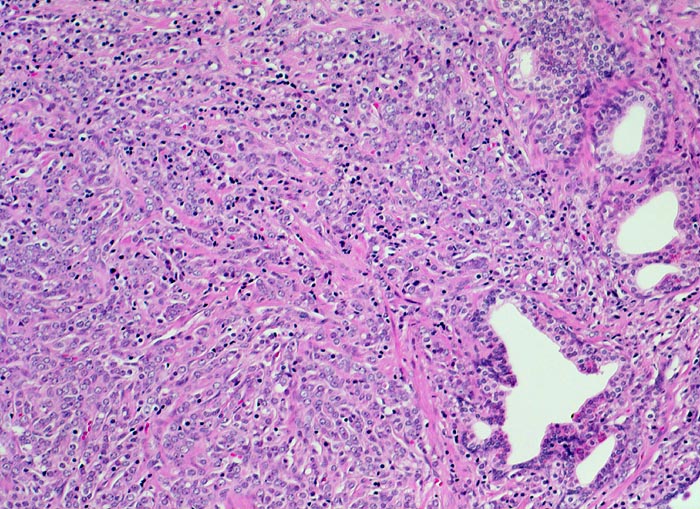

Adenokarzinom der Prostata

Neben einzelnen benignen grossen Prostatadrüsen findet sich ein diffuses Infiltrat schlecht geformter, sehr kleiner, dichtliegender maligner Drüsen und einzeln liegender Tumorzellen mit grossen Zellkernen und wenig Zytoplasma.

Schlecht geformte, miteinander fusionierte Karzinomdrüsen, die sich infiltrativ zwischen normalen Drüsen ausbreiten entsprechen einem Gleason Grad 4. Dissolut liegende Tumoreinzelzellen oder Tumorzellstränge, die keine drüsigen Strukturen erkennen lassen, entsprechen einem Gleason Grad 5 (überwiegendes Muster im vorliegenden Bildausschnitt).